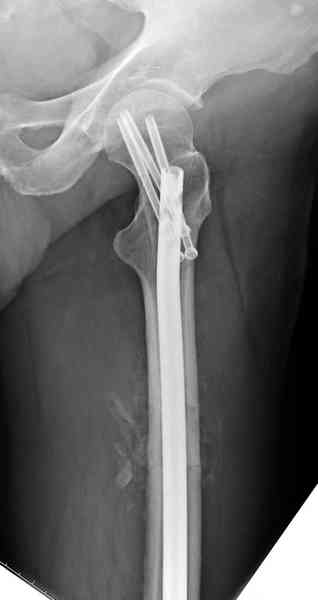

В первый же день произведено антеградное штифтованием DePuy Trochanteric Nail.

На второй день (7) обнаружен пропущенный перелом,

и проведены шурурпы через и спереди штифта без удаления.

Послеоперационные снимки